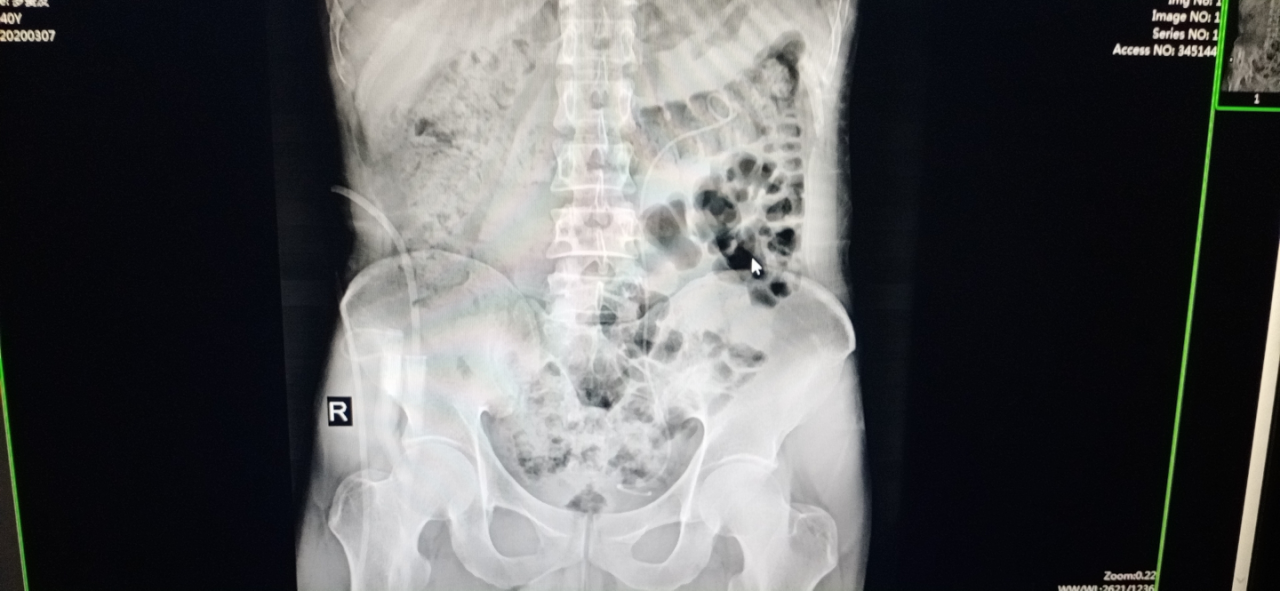

患者:罗先生; 年龄:40岁;15年来,双肾因巨大结石而导致双肾重度积水,双侧功能严重受损,甚至面临多发、复杂结石病变的威胁。

入住我院泌尿外科之后,在完善相关检查之后,泌尿外科团队确诊其为:双肾结石导致双肾重度积水,双侧功能严重受损,并面临多发、复杂结石病变的威胁。 因为患者病情重且较为复杂,双肾结石巨大,若进行手术,存在出血、感染加重的风险,且结石残留大。术中或术后出现大出血并无法止血,可能需栓塞肾动脉止血,导致肾功能不全(尿毒症),感染严重时也可引起尿源脓毒血症的发生导致患者死亡。但是如果不及时进行处理,肾里面巨大的结石长期刺激黏膜会引起慢性炎症或感染,严重者甚至会引发癌变。结石还可能引起尿路梗阻,尿路梗阻后可能导致输尿管和肾盂扩张、积水,损伤肾脏功能,严重时可造成肾功能不全(尿毒症),后期病情会越来越严重,直至肾功能完全丧失。 面对如此复杂的病情,泌尿外科团队反复进行讨论、仔细研判,一致认为:患者的治疗刻不容缓,因右肾结石较大、多发、复杂、感染,为保护左肾功能及避免脓毒血症,结石复杂且合并严重感染,不能一次性清除所有结石,并且手术时间不宜过长,需分期手术。